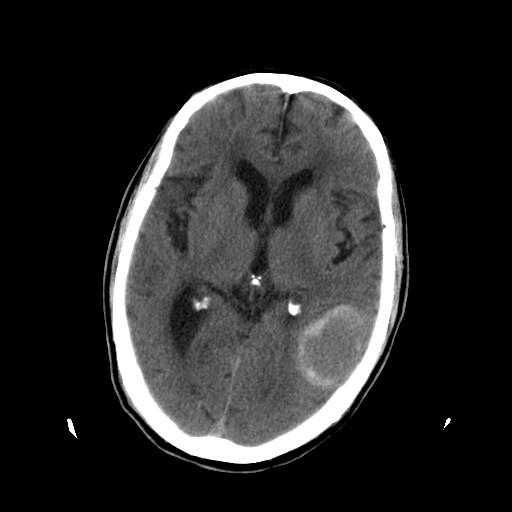

患者,男,70岁,清晨(10小时前)无法自行起床,家人无法唤醒,现昏迷,大小便失禁

左颞枕叶交界区可见类圆形高密度区,边缘可见环形更高密度影,并夹杂有点状钙化影,占位效应明显,未见明显水肿影,考虑脑膜瘤出血

肿快呈以等密度为主的等高密度影,占位效应不是很明显,只是左枕角受压,肿块内侧似有低密度改变.

脑膜瘤伴出血或伴钙化(因未测ct值).

左颞枕叶交界区可见类圆形高密度区,边缘可见环形更高密度影,侧脑室后角明显受压而周围未见明显水肿.考虑脑膜瘤伴出血可能性大不排外血管畸形.建议mr进一步检查.

左侧颞枕叶交界区见类圆型等高密度混杂影,边缘可见高密度影环绕,同侧侧脑室后脚受压变形,周边围见明显水肿影. 结论:脑膜瘤首先考虑.

左颞枕叶交界区的类圆形高密度区首先考虑脑膜瘤卒中,病人左侧小脑半球的还有多个囊性低密度,要考虑同时伴有梗塞的可能。